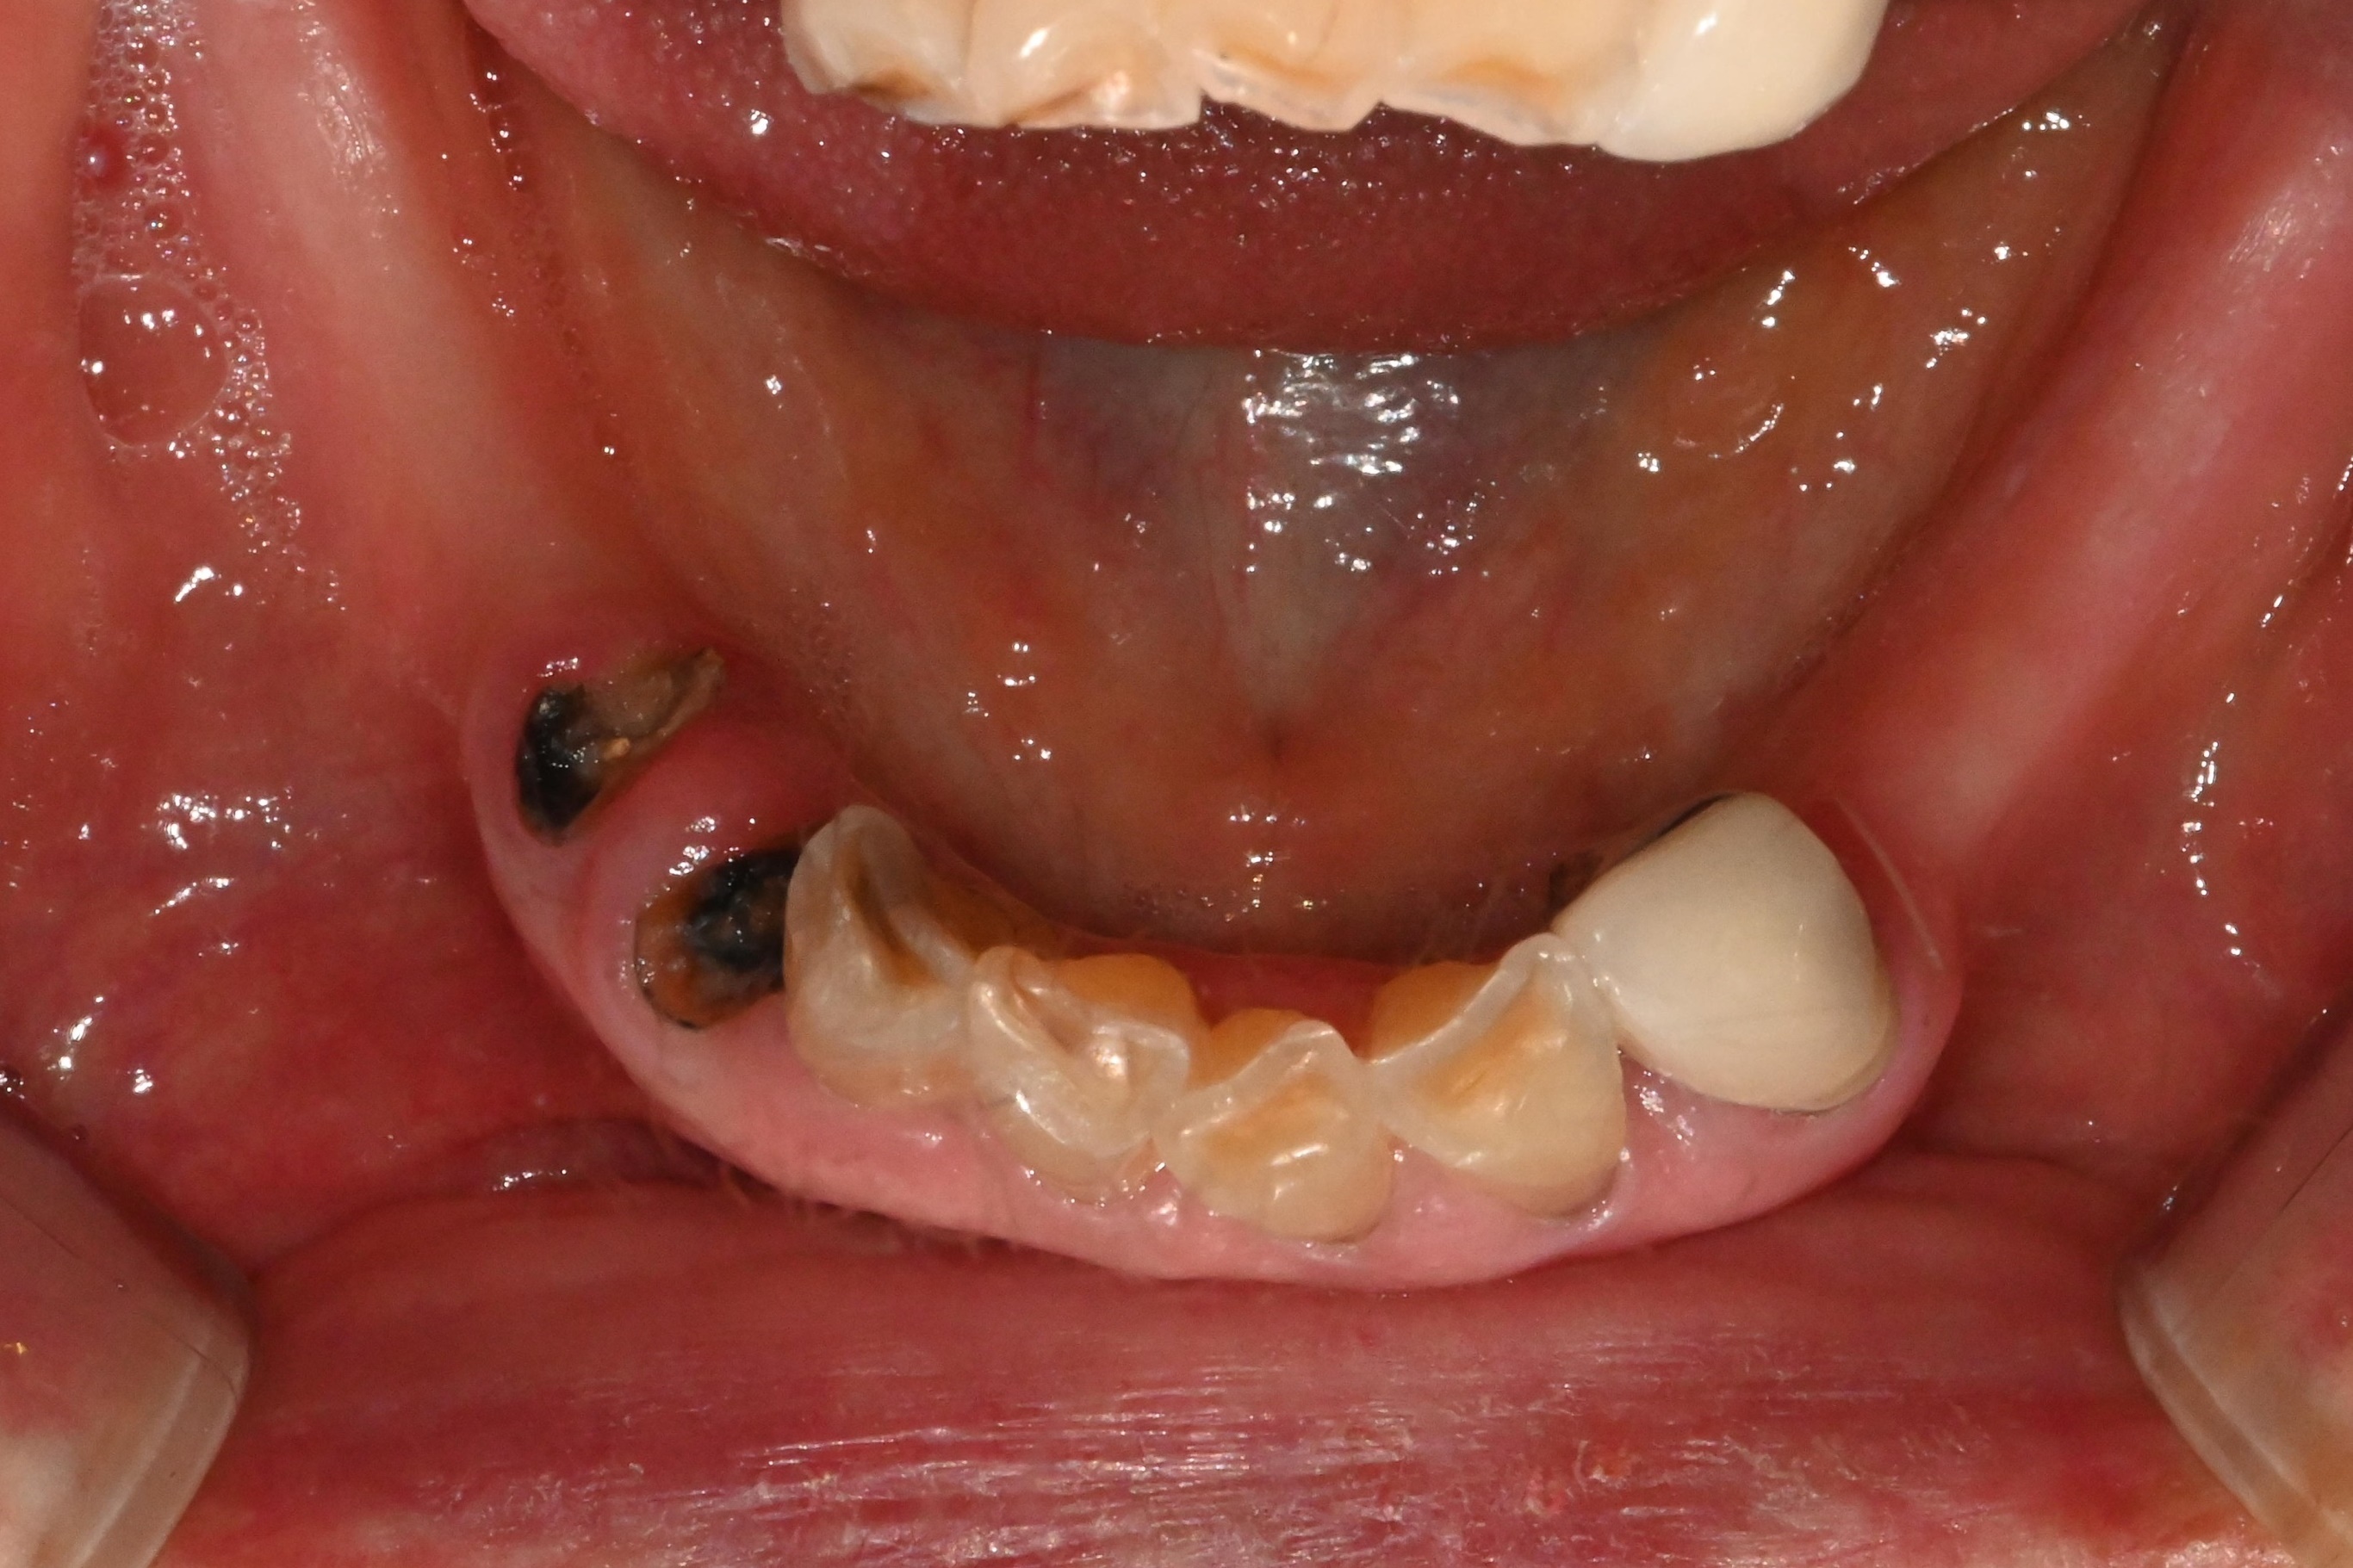

이분 같은 경우

아래 앞니는 염증으로 인해

이미 흔들리고 있었고

겉으로 보기에도

잇몸이 많이 부어 있었지만,